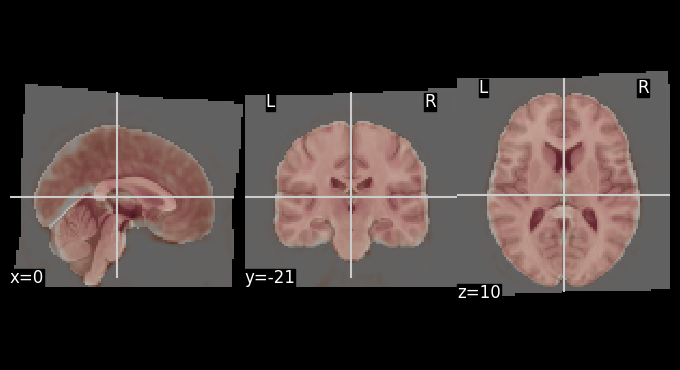

Let’s use add_contours as another visualization option for checking coregistration by overlaying the MNI template as contour (red) on top of mean functional image (background):

# Create a binary mask of the template

template_mask = math_img("img > 0.1", img=template)

display = plotting.plot_anat(mean_bold, title="Edges of MNI template on mean BOLD", colorbar=False)

display.add_contours(template_mask, colors='r')